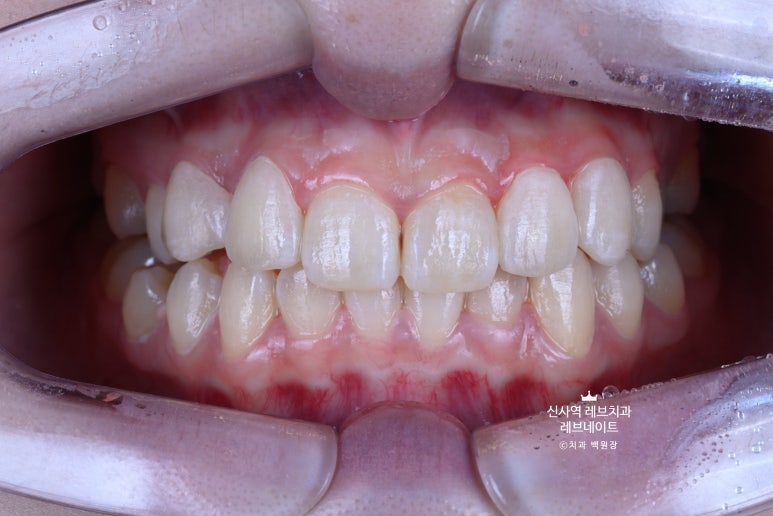

Before & After

지금 보면 이제 자연스러워 보이는 이 모습이

원래는 이런 부정교합의 모습이었다는 것!

비교해보면 더 확연히 마음에 닿으실 거에요.

뭔가 가지런히 정돈되서, 환자분도 저희들도 만족하고 뿌듯했던 케이스였습니다!

어쨌든 앞에서 보니, 확실히 다르더라구요.

아주 어려운 상황에서, 자연스러운 아름다움을 잘 찾아낸 것 같습니다.